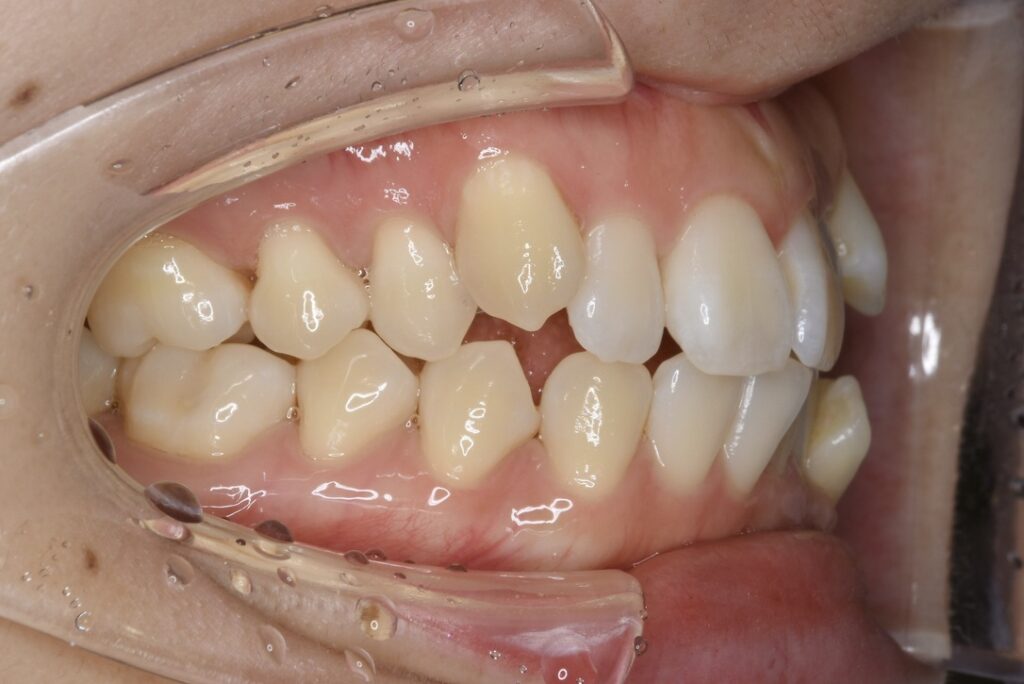

| 主訴 | 上の歯が出ていて、横顔が気になる。 |

|---|---|

| 診断名・主な症状 | 両側第一小臼歯の鋏状咬合を伴う上顎前突 |

| 年齢 | 13歳 |

| 治療内容 | 上下の歯並びの幅を拡げつつ、咬合関係を改善しました。 |

| 使用装置 | 表側矯正(ワイヤー) 矯正用ミニインプラント |

| 抜歯部位 | 抜歯なし |

| 治療期間 | 1年2ヶ月 |

| 通院回数 | 17回 |

| 費用 | 86万円程度(税別) 254 |

| リスク・副作用 | 痛み、歯肉退縮、歯根吸収、抜歯に伴う出血や腫れが生じることがあります。 |